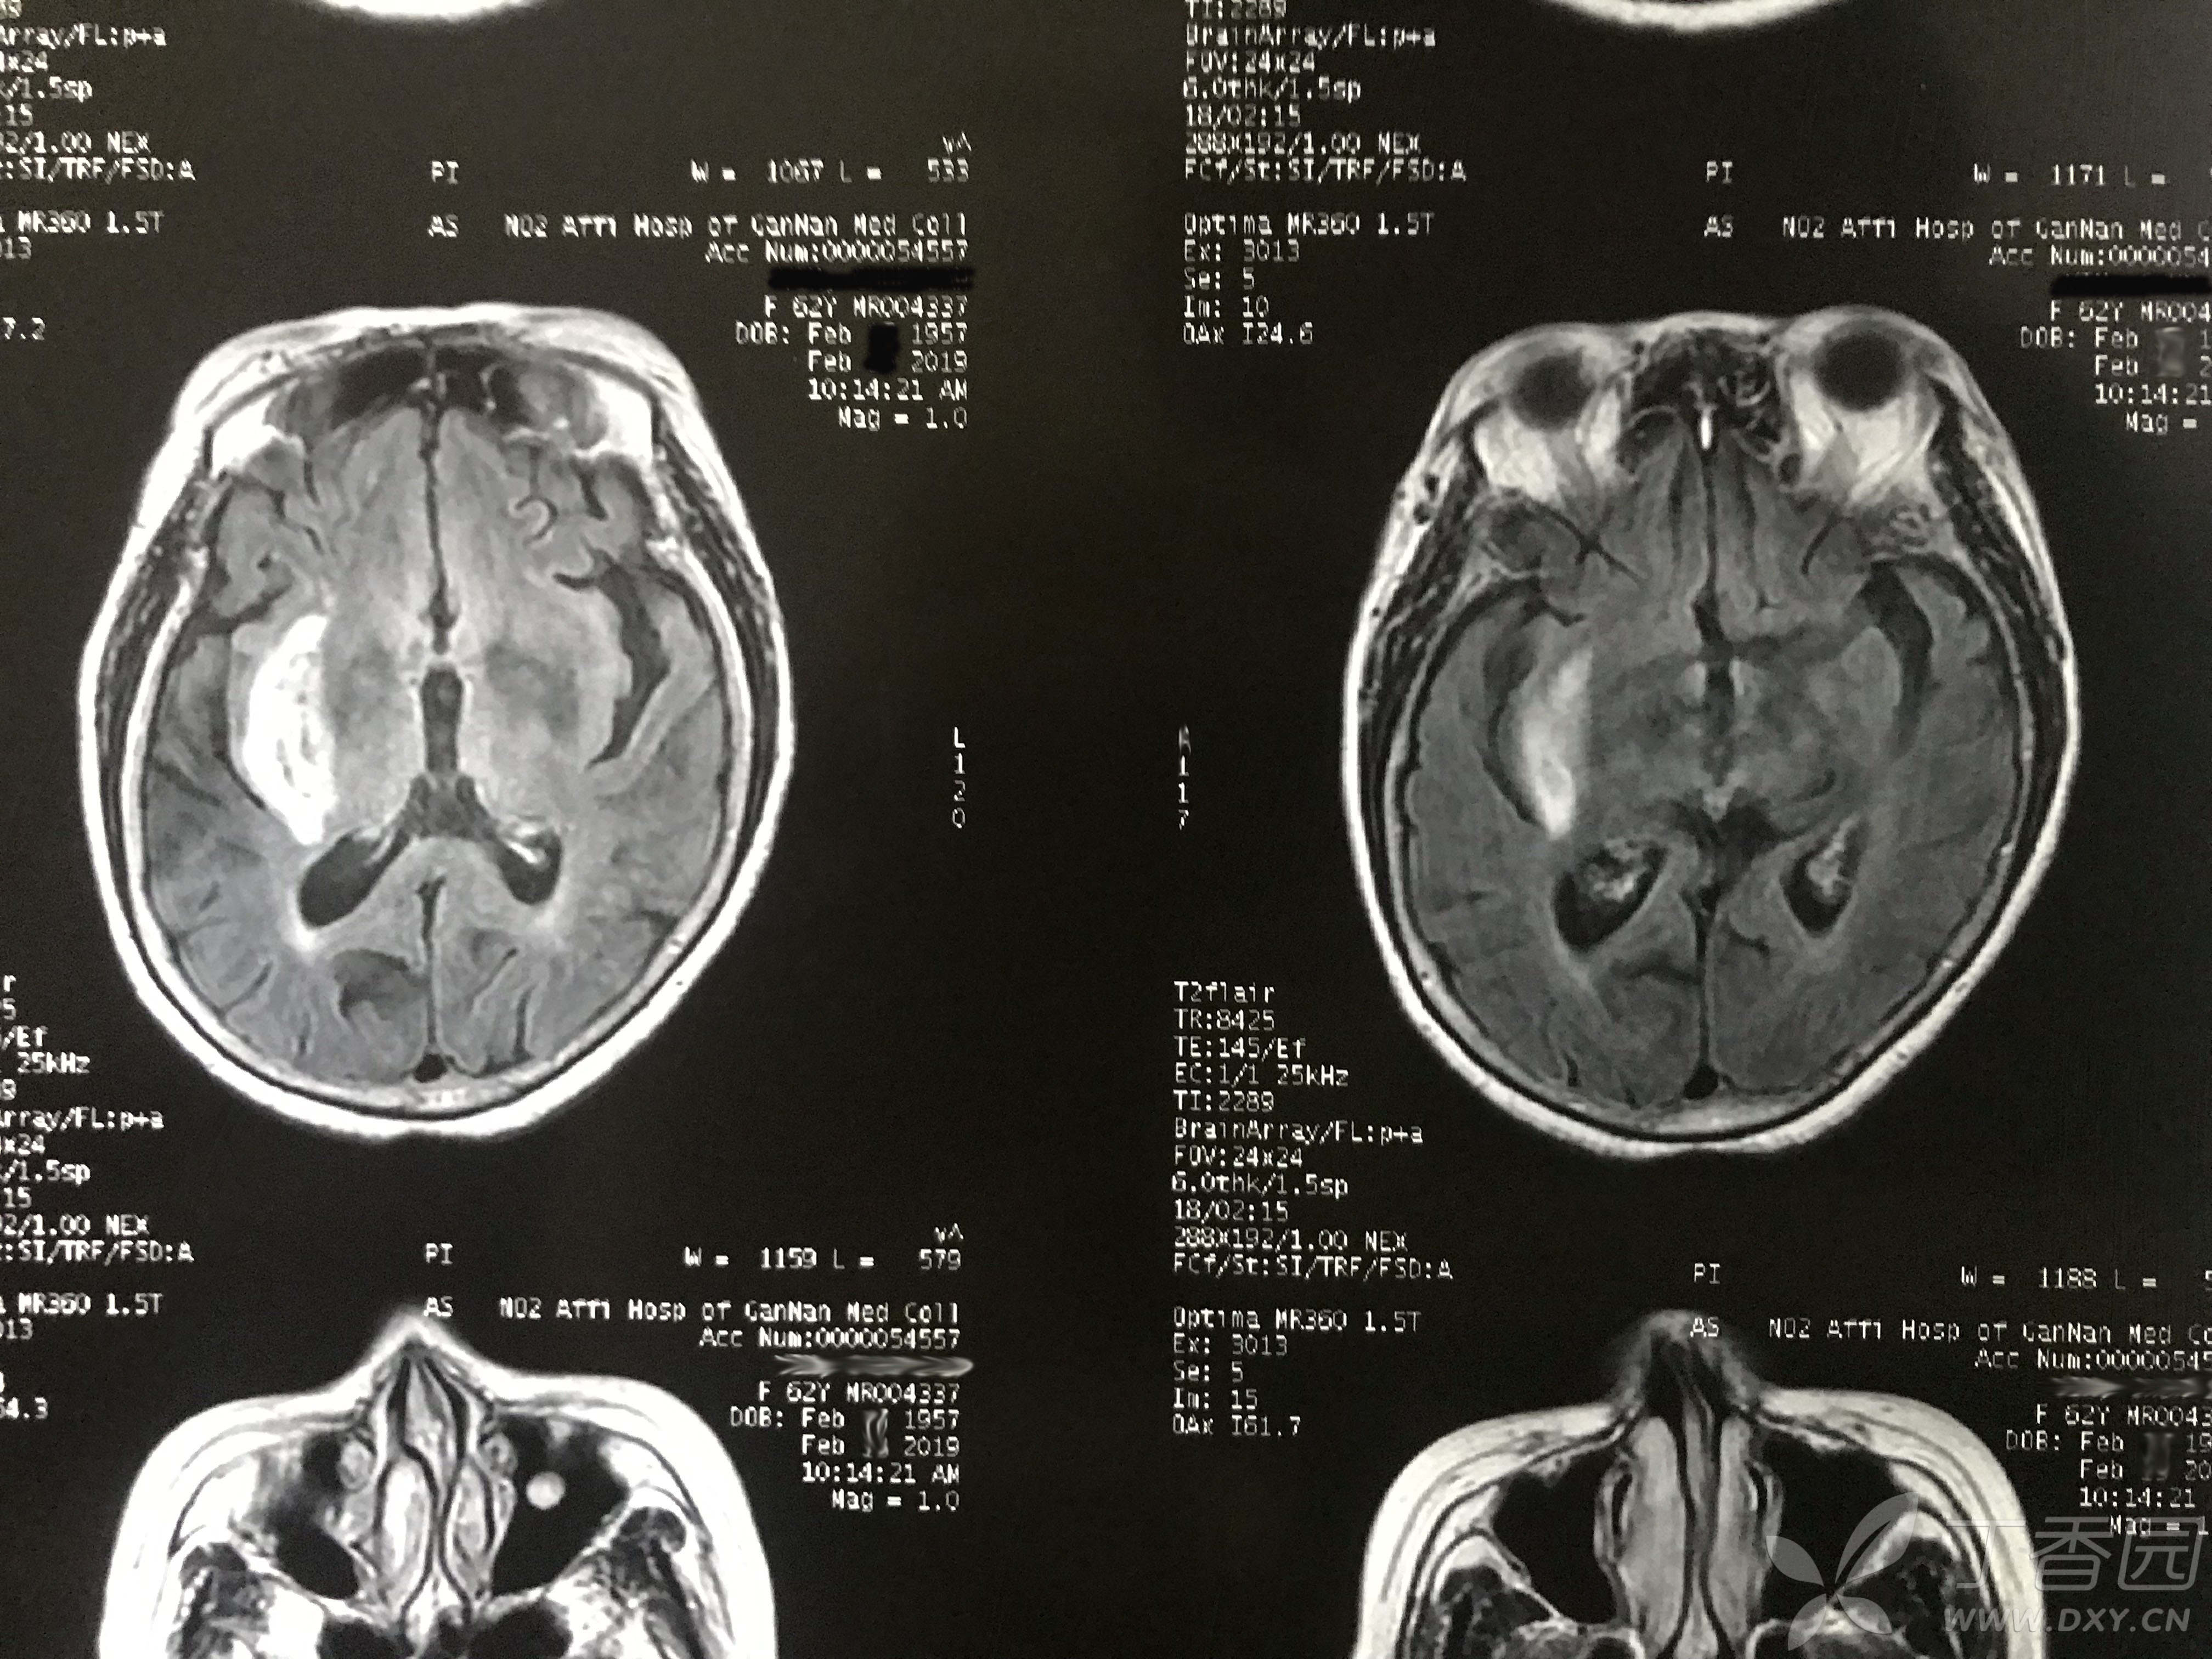

头部核磁共振太痛苦了是什么意思

核磁共振是利用磁场成像,没有放射性,是非常安全的一种常用无创检查方法,尤其是对头部脑干和小脑部位的检查最为清晰,对人体也是无害的做头部核磁共振检查的时候,不会造成任何的痛苦与其他辅助检查手段相比,核磁共振具有成像参数...